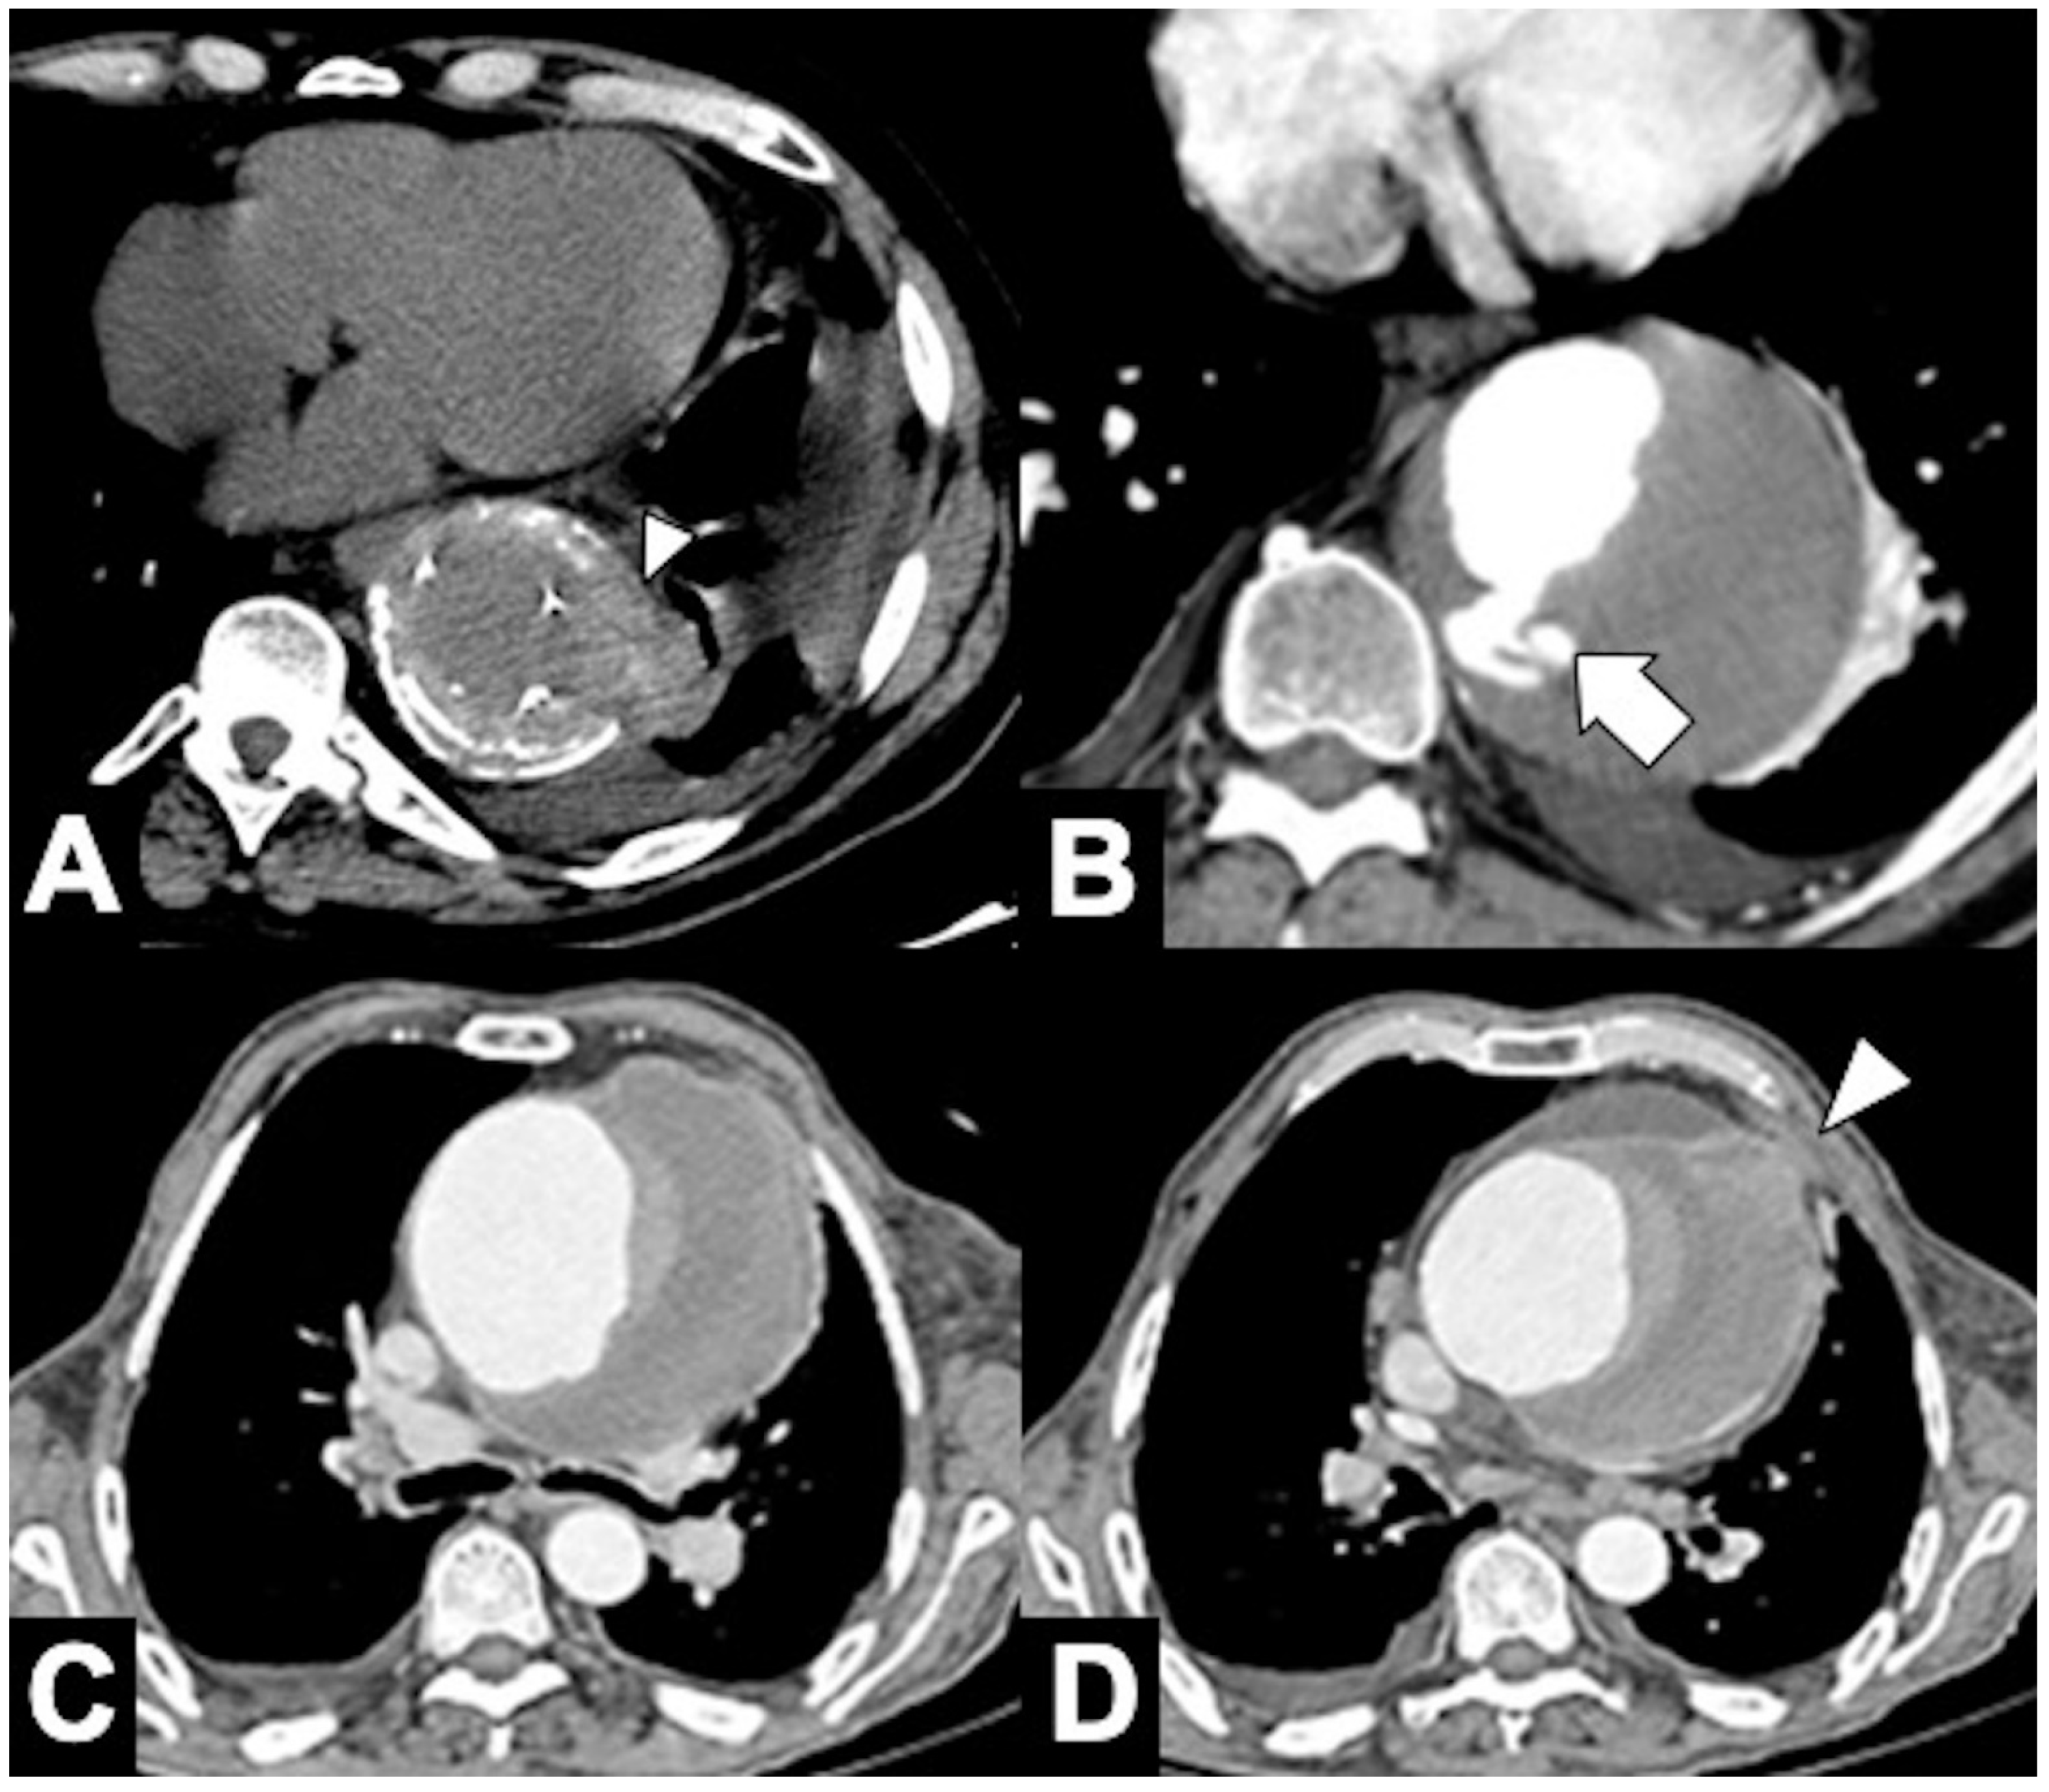

Because an abdominal aortic aneurysm occurs in 28% of patients with a TAA, it is important that the initial evaluation includes the entire thoracoabdominal aorta. TAAs are classified by location as affecting more commonly the ascending aorta (36%), aortic arch (34%), or DTA (30%) [103]. Annuloaortic ectasia is a condition with dilated sinuses of Valsalva along with effacement of the sinotubular junction (STJ) producing a pear-shaped ascending aorta commonly seen associated with Marfan syndrome and other connective tissue disorders (Figure 11A,B). The Crawford classification modified by Safi describes five types of thoraco-abdominal aortic aneurysms [104]. In the evaluation of TAA, CTA accurate depiction of aortic caliber on centerline imaging, morphology, relationship to the aortic arch vessels and the presence of thrombus or ulceration are of importance in deciding whether and how to intervene [104,105]. Accurately measured maximal aortic diameter is currently the primary metric used to guide surveillance strategy and the timing of surgical/endovascular intervention for patients with TAA (Figure 11C). The generally accepted aneurysm growth rate is 4 mm/year, and intercurrent dissection is associated with a more rapid growth rate. When the size of the aorta reaches its biomechanical “hinge point,” usually about 5.5 cm in diameter for ascending aorta and 7 cm for DTA, wall integrity rapidly declines, growth accelerates, and the incidence of complications rapidly increases. A rupture occurs when mechanical stresses on the wall exceed the wall strength, and as dictated by the law of Laplace, the rupture risk increases with aneurysmal size (Figure 11D) [106,107]. Clinical subtle and non-specific symptoms may already correspond to clear radiological signs of impending rupture. As far as the most accepted widespread criteria are represented by the maximum diameter and the expansion rate, there are other important imaging features that radiologists must be aware of, to promptly detect potentially life-threatening conditions (Table 6). These features are considered by most authors as signs of impending rupture (SIR) and include, amongst others, (1) a hyper-attenuating crescent sign, (2) focal wall discontinuity of circumferential calcifications (Figure 12A), (3) aortic bulges or blebs, and (4) a draped aorta sign or periaortic stranding [108,109]. These signs are mostly based on CT characteristics of the mural thrombus. Aneurysms are indeed often characterized by a thrombus lining the walls and by a patent lumen. As some authors consider the width of the mural thrombus a protective factor for aneurysm stability, the reduction in its width is considered a criterion of higher rupture risk [110]. Amongst the aforementioned SIR, the “hyperattenuating crescent sign” results from intraluminal blood creating a fissure that transits through the unstable mural thrombus to the intimal margin, forming a typical semilunar shape [111].

Figure 11. CTA of thoracic aorta aneurysms. (A) Marfan syndrome, a multisystem connective tissue disease caused by a defect in the protein fibrillin 1, and annuloaortic ectasia in a 42-year-old man. Sagittal MIP reconstruction image shows a proximal dilatation of the aortic anulus (1), sinuses of Valsalva (2) along with effacement of the STJ (4) producing a pear-shaped ascending aorta (3). (B) Axial CTA image shows sinuses ectasia in the same patient. In Marfan syndrome, a cut-off value of 5 cm of the ascending aorta diameter is recommended for surgical repair. (C) Axial CTA image shows a 12 cm ascending aorta aneurysm (asterisk) and a large mediastinal effusion. The risk of rupture of TAAs increases with size of the aneurysm according to Laplace’s law. (D) Axial CTA image shows a ruptured atherosclerotic aneurysm of the descending thoracic aorta. Note the high-attenuation fluid in the right pleural space, representing acute hemothorax (asterisk), and contrast medium extravasation from the aortic lumen (arrow).

Figure 12. CTA findings in impending rupture of the thoracic aorta aneurysms. (A) Missing calcium sign (arrowhead). (B) Thrombus fissuration (arrow). (C) Hyperattenuating crescent sign, periaortic stranding sign, and contour irregularity of the aneurysm. (D) Periaortic fat stranding blurs a focal area of the mediastinum and extends to the chest wall representing an inflammatory process (arrowheads) [111].

Discontinuity of thrombus circumferential calcification, also known as a “missing calcium sign,” refers to the focal interruption of mural calcification, indicating the site of impending rupture, especially if the aortic lumen tapers toward the focal discontinuity (tangential calcium sign). It is worth mentioning that these are the commonest signs associated with asymptomatic patients who developed sudden symptoms later [21]. Aortic bulging or blebs and contour irregularity of the aneurysm refer to the focal bulging of the aneurysm wall, which generally indicates loss of elastic fibers and inflammatory changes that underlie a potential rupture [112]. This sign together with the “draped aorta sign,” in which there is loss of the normal fat plane between the aneurysm and the vertebral bodies, with a characteristic wavy shape of the posterior aortic wall, are considered less-dangerous findings with no rupture demonstrated on follow-up imaging in most cases. On the other hand, periaortic fat stranding can indicate extraluminal rupture (Figure 12C,D) [112,113,114].